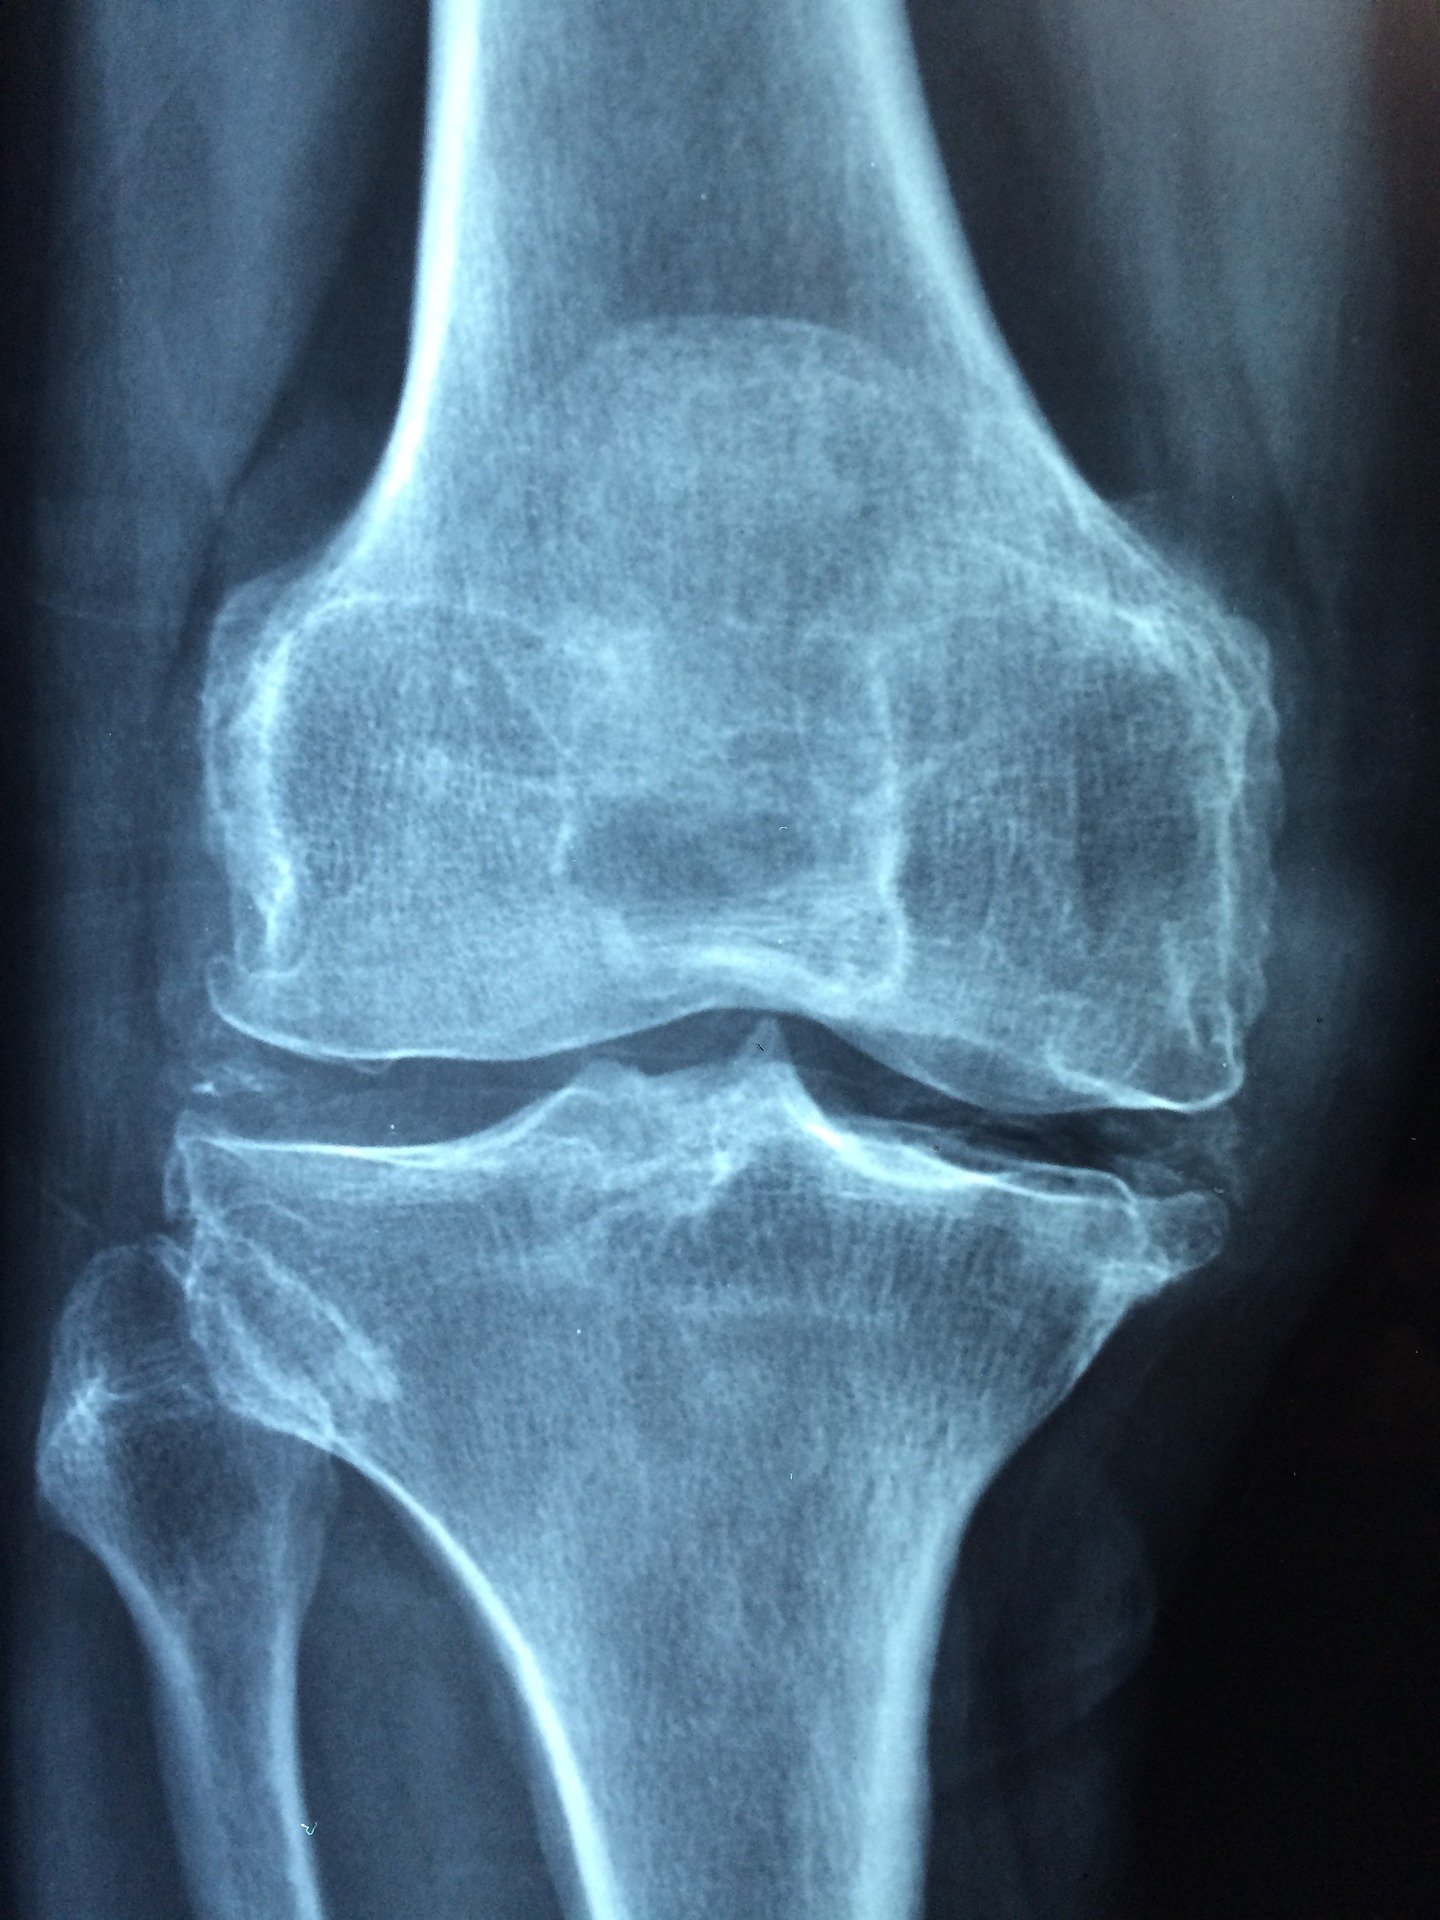

Osteoporosis, a disease which reduces bone strength and increases bone fracture risk, is a major national health issue and estimated to affect over 900,000 Australians. The cost of osteoporosis and fracture in Australia is $3.4 billion annually.

From age 50, bone fractures affect one in two women and one in three men. For women, the lifetime risk of a hip fracture is equal to or higher than the risk of developing an invasive breast cancer.

With each fracture, the risk of future fracture increases two-fold and studies have shown that pre-existing fractures increase the risk of premature death by about 50% in both men and women. One in three adults over 50 dies within 12 months of sustaining a hip fracture.